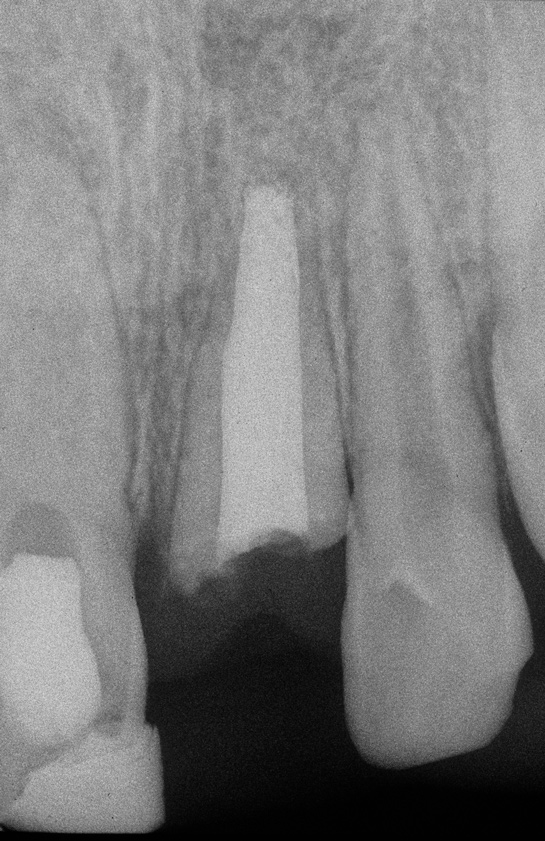

Fig 2. Age 8. Radiograph of teeth Nos. 8 and 9 at initial examination.

Figure 2

The patient's endodontic examination revealed a flexible splint from teeth Nos. 7 through 10 (Figure 1). Tooth No. 8 had a 3 mm x 3 mm class II fracture of the mesioincisal portion of the crown. Tooth No. 9 had a class IV fracture of the crown running labiopalatally from the remaining 2 mm of the crown to bone level on the palatal. A pulpotomy had been performed on the exposed pulp. Both teeth exhibited class III mobility. Teeth Nos. 7 through 10 did not respond to cold testing. None of the teeth were tender to palpation, and only tooth No. 9 had a slight positive response to percussion. Periodontal probings of tooth No. 8 were 4 mm to 5 mm on both the labial and palatal aspects. There was a narrow 12 mm probing on the straight palatal of No. 9; the remaining probing depths were 4 mm to 5 mm.2 A periapical radiograph showed both teeth Nos. 8 and 9 to have incompletely formed roots with wide-open foramina (Figure 2).

Allowing for differences in radiographic angulation, the apices of the retained roots remained in a similar position relative to the apices of the adjacent teeth as did the coronal edges of the root relative to the CEJs of those teeth (Figure 3, Figure 7, and Figure 10). It appears that the retained roots preserved the developing ridge associated with them in a manner similar to the developing ridge next to the injury site during the child's 11 years of growth. The final result was an intact alveolar ridge with an adequate labial plate at the proper level for an implant (Figure 11).